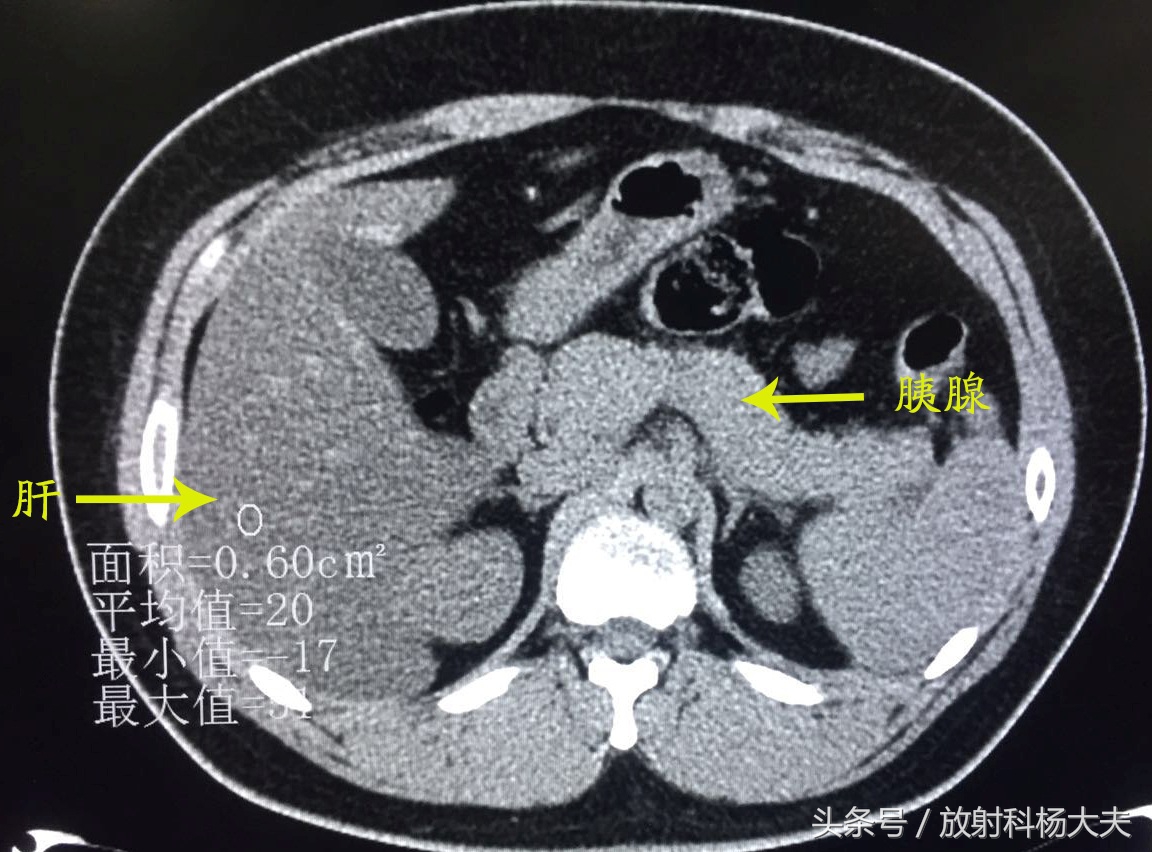

当时治疗后复查:

胰周渗出基本吸收了,脂肪肝较前也有所好转了。

详细问了一下病史,这个29岁的小伙子有高脂血症,5年了。那么,他的高脂血症和胰腺炎反复发作有关系吗?

近几年发现高脂血症是继胆源性、酒精性之后导致胰腺炎的常见危险因素,CT 表现以重症胰腺炎和重度脂肪肝为主,随着血脂水平下降,脂肪肝和胰腺炎影像表现同步好转,排除胆源性和酒精性原因,应首先考虑高脂血症性胰腺炎。